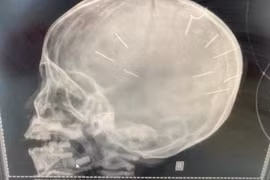

Trong lúc đùa giỡn cùng bạn, bé trai 13 tuổi bị dao đâm thủng hộp sọ phải nhập viện cấp cứu.